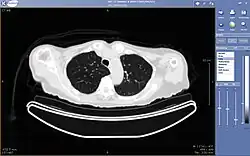

Teleradiology

A CT exam displayed through teleradiology

Teleradiology is the ability to send radiographic images (X-rays, CT, MR, PET/CT, SPECT/CT, MG, US...) from one location to another.[88] For this process to be implemented, three essential components are required: an image-sending station, a transmission network, and a receiving-image review station. The most typical implementation is two computers connected via the Internet. The computer at the receiving end will need a high-quality display screen that has been tested and cleared for clinical purposes. Sometimes the receiving computer will have a printer for convenience.

The teleradiology process begins at the image-sending station. The radiographic image and a modem or other connection are required for this first step. The image is scanned and then sent via the network connection to the receiving computer.

Today's high-speed broadband-based Internet enables the use of new technologies for teleradiology: the image reviewer can now have access to distant servers in order to view an exam. Therefore, they do not need particular workstations to view the images; a standard personal computer (PC) and digital subscriber line (DSL) connection is enough to reach Keosys' central server. No particular software is necessary on the PC, and the images can be reached from anywhere in the world.

Teleradiology is the most popular use for telemedicine and accounts for at least 50% of all telemedicine usage.